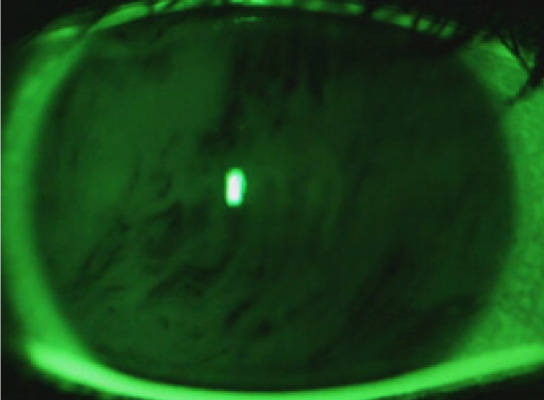

Была проведена оценка состояния глазной поверхности у пациентов обеих групп до и после проведения КРХ с помощью универсального тест-опросника по выявлению клинических признаков синдрома сухого глаза (OSDI), результаты которой представлены в табл. 1. Результаты показали отсутствие субъективных признаков ксероза глазной поверхности в первой и второй группах до проведения КРХ, и появление легкой и умеренной степени выраженности у пациентов в обеих группах в сроки наблюдения на 1-е сутки и через 1 месяц. Через 3 месяца легкая и умеренная степень выраженности ССГ отмечалась только у пациентов из первой группы, однако уже к 6-му месяцу наблюдения в обеих группах отмечалась легкая степень выраженности ССГ и отсутствие субъективных жалоб. Результаты общих стандартных офтальмологических методов исследования глазной поверхности на всех сроках наблюдения в обеих группах показали отсутствие патологических признаков при проведении биомикроскопии переднего отрезка, как показано на рис. 1, и окрашивании глазной поверхности раствором флюоресцеина.

Рис. 1. Биомикроскопия